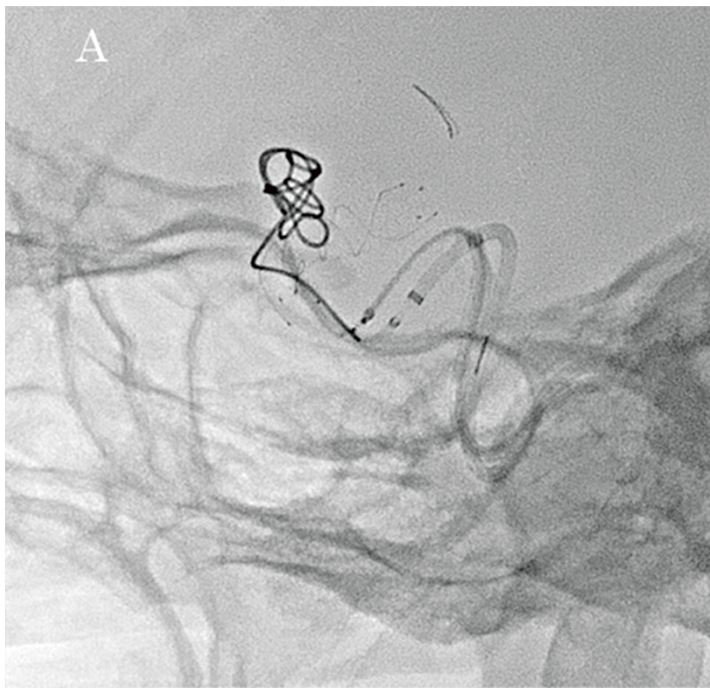

Було необхідно встановити стент з початку передньої хореоїдної артерії до C3-4 (класифікація Фішера), тому було вибрано LVIS (4,0 мм × 17 мм; Terumo Corporation, Японія). Процедура проводилась за допомогою техніки "jailing",1) в якій мікрокатетер для емболізації вводиться в аневризму перед встановленням LVIS. В якості якоря для навігації мікрокатетера використовувався Axium™ Prime Frame (5 мм × 10 мм; Medtronic Japan Co., Ltd., Японія), після чого було встановлено LVIS.

Флюорографічні зображення, отримані за допомогою Hi-Def Detector, дозволили чітко спостерігати поведінку котушки та мікрокатетера, а також розгортання стенту за допомогою високороздільних зображень, що забезпечило надзвичайно ефективну підтримку під час процедури (малюнки 2A та 2B). Далі, за допомогою опції Alpha CT (конусно-променевої комп'ютерної томографії), було підтверджено стан розгортання стенту та затискування головної судини (малюнки 3А та 3В), після чого проведено додаткову емболізацію з використанням спіральних котушок в зоні втікання до аневризми. Лікування було завершено із щільністю запаковування котушкою у 28,24%. Наявність або відсутність інтранкраніального крововиливу було підтверджено за допомогою Alpha CT.

Малюнок 2A: Флюорографічне зображення, отримане за допомогою Hi-Def детектора (3 дюйми) під час розміщення LVIS.